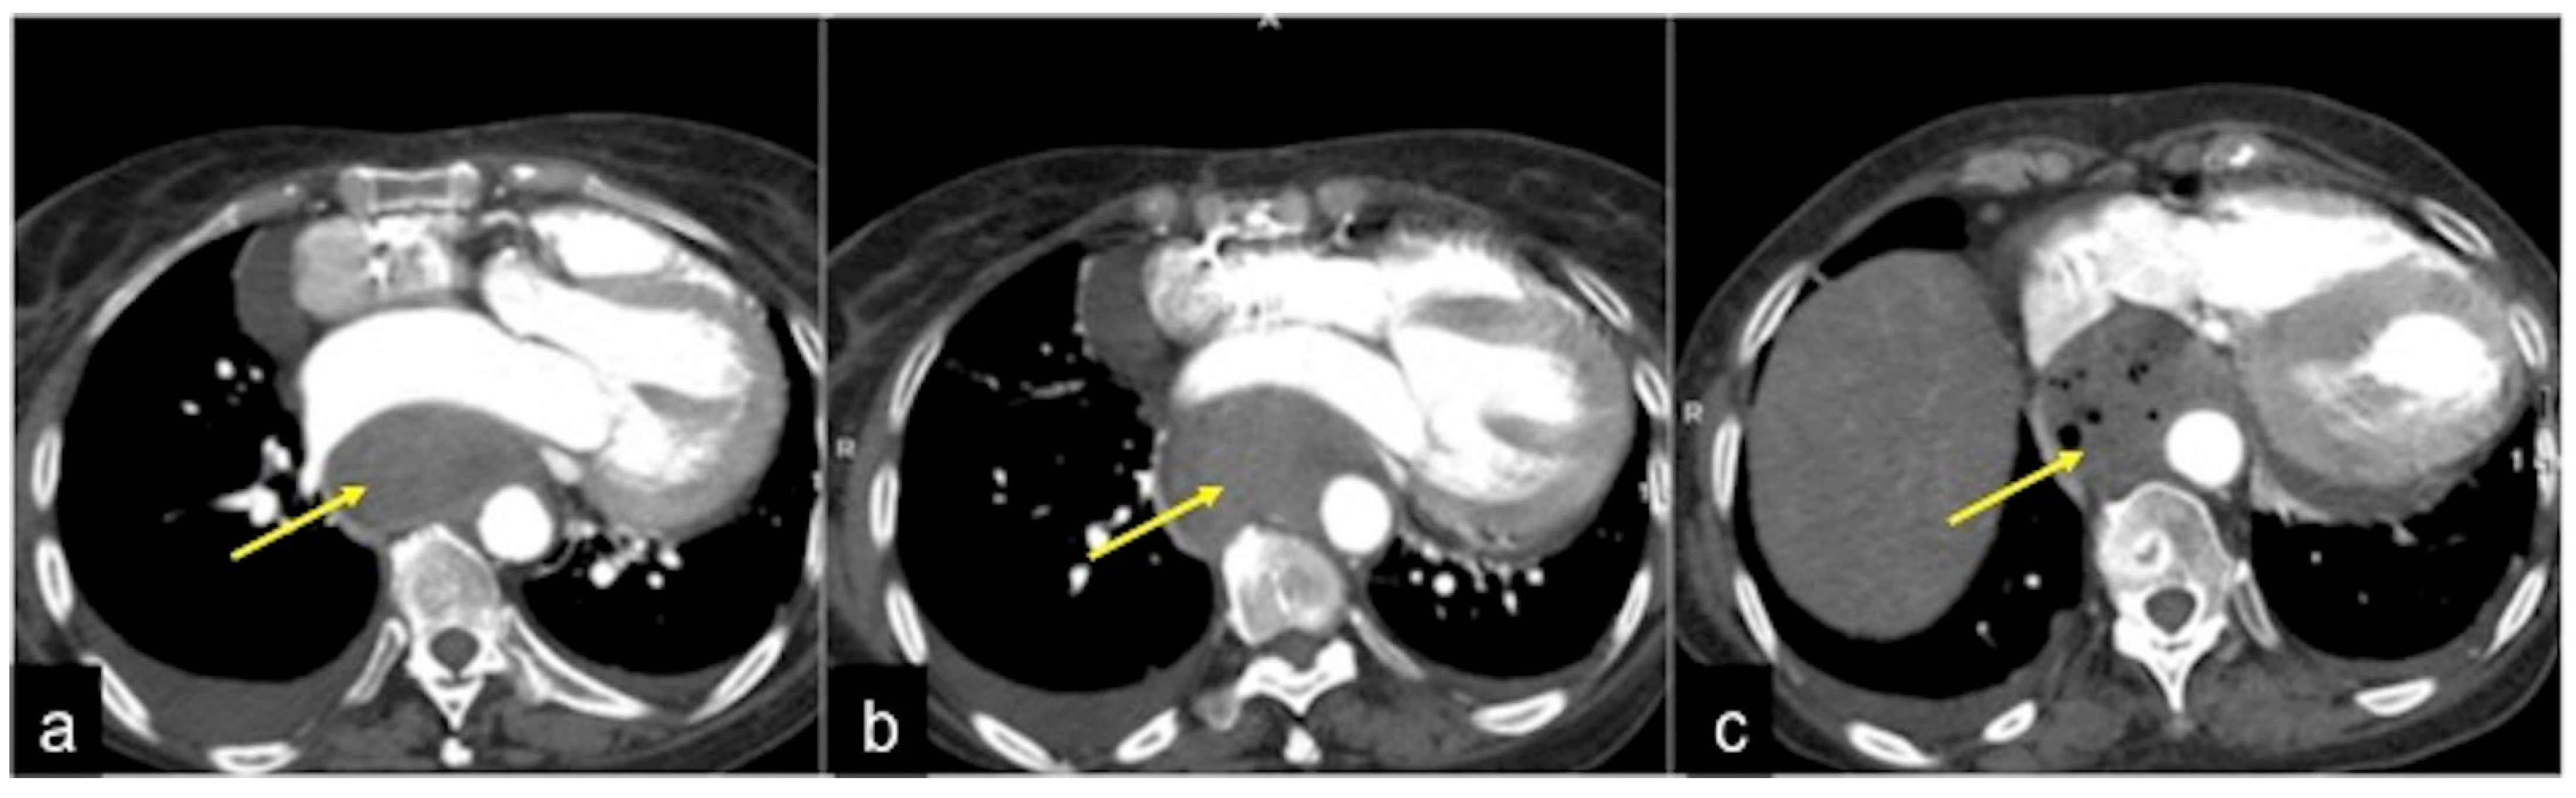

| Aorto-Enteric Fistula (Figure 31) | Bleeding in a patient with a history of surgery for aortic aneurysm. | A connection between the aorta and the intestinal lumen. Absence of adipose cleavage planes. |